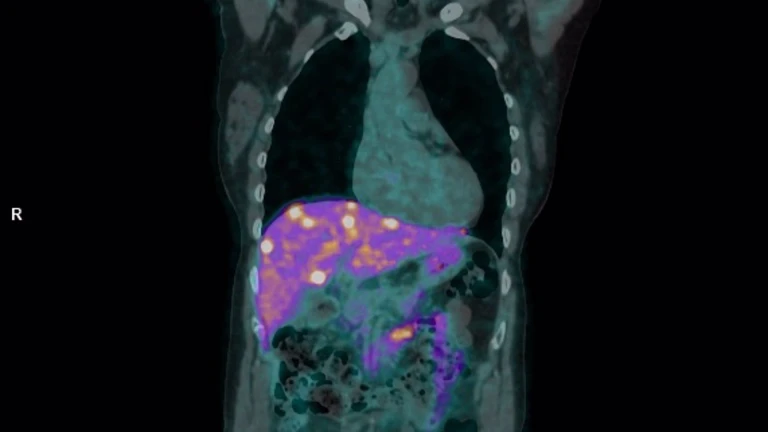

El Hospital Universitario Reina Sofía de Córdoba ha logrado un nuevo hito médico al convertirse en el primer centro de Europa en utilizar el radiofármaco cobre-64 (64-Cu) Dotatate para el diagnóstico de tumores neuroendocrinos. Este avance, pionero en el continente, mejora la precisión de las pruebas de imagen y abre la puerta a nuevas aplicaciones en el campo de la teragnosis, que combina diagnóstico y tratamiento en una sola estrategia clínica.

El cobre-64 Dotatate es un trazador de última generación que se emplea en estudios PET-TAC para detectar tumores que expresan receptores de somatostatina. Gracias a esta tecnología, es posible visualizar lesiones tumorales con mayor claridad, facilitando así una estadificación más precisa y una planificación terapéutica más ajustada a cada paciente.

Según ha explicado el jefe de servicio de Medicina Nuclear del hospital, Juan Antonio Vallejo, este nuevo radiofármaco “ofrece mayor calidad de imagen, mejor contraste de las lesiones y una ventana temporal más amplia, tanto para su suministro como para la obtención de imágenes”. Esta mejora logística permite una organización más eficiente del diagnóstico, especialmente en pacientes que requieren un seguimiento estrecho o una planificación individualizada del tratamiento.